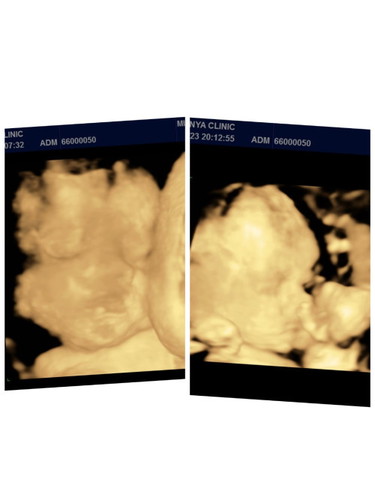

บ้านไหนมีลูกเเฝดบ้างค่ะ

ปกติเเม่ๆคลอดน้องเเฝดกี่วีคค่ะ #ขอบคุณสำหรับคำตอบค่ะ บ้านนี้34วีคเริ่มไม่ไหวจริงๆค่ะ